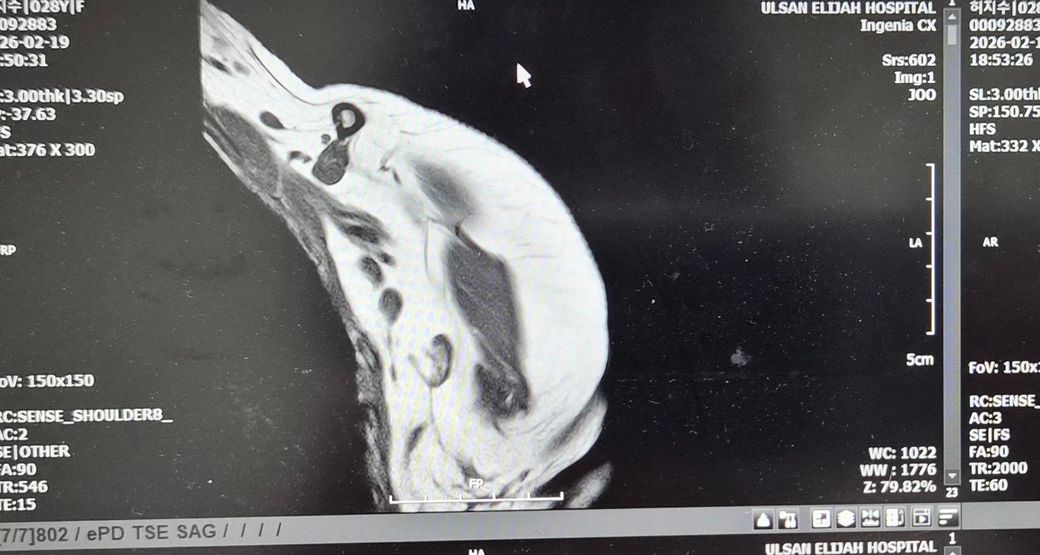

어께MRI판독좀 해주세요!어떤가요?

뺄수밖에 없었어요.누워서 안정취하다가 수납하고갔어요.그다음날 종합병원정형외과가서 접수하고 기다렸어요. 들어갔더니 의사가 힘줄에는 다 이상이 없데요.뼈가 (견봉쪽?)골절되면서 붙으면서 뼈가 위로조금 오른쪽이랑 다르게 올라갔데요 그래서 아프면 주사맞자고해서 주사대기중이였어요.옷갈아입고 기다렸어요.

올려주신 MRI사진은 화면 촬영본이라 정확한 판돈까지는 어렵지만, 담당 의사가 말씀하신 것처럼 회전근개 힘줄 자체의 명확한 완전파열 소견은 없어 보이는 경우로 이해됩니다. 설명해주신 내용상 어깨 위쪽 뼈 쪽 골절이 치유되는 과정에서 약간 위로 붙어 형태가 변형되었고, 그로인해 어깨를 들때 힘줄과 뼈 사이 공간이 좁아져 마찰이 생기는 충돌 증후군 형태일 가능성이 높아 보입니다. 주사 치료는 보통 염증을 줄이기 위한 스테로이드+국소 마취제 주사이며, 약물이 하얗고 양이 많으며 들어갈때 아픈것은 비교적 흔합니다. 주사 맞은 당일저녁에 헬스장에서 찌릿한 통증이 생긴것은 힘줄이 새로 찢어졌다기보다는 주사 후 자극+기존 충돌부위 자극 때문일 가능성이 훨씬 큽니다. 현재로서는 최소 1주일 정도는 상체웨이트 운동을 쉬고, 얼음찜질과 가벼운 가동범위 운동만 하는것이 좋습니다. 이후 통증이 줄어들면 가벼운 밴드 운동부터 재개하는 것이 안전합니다. 빠른쾌유를 빕니다!

올려주신 사진은 정확한 컷이 아니라 판독이 어렵습니다